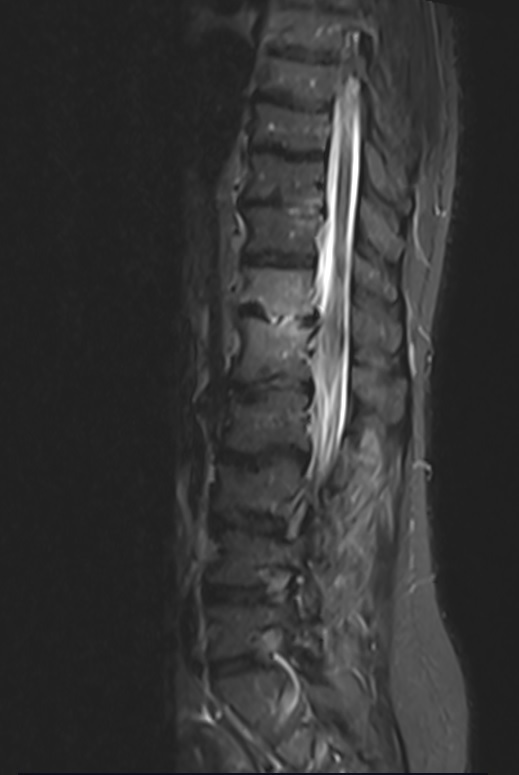

Une imagerie est réalisée, présentée ci-dessous (figure 4) :

Voici une séquence d’IRM séquence T2 STIR, puis T1 avec injection de gadolinium (figures 4 et 5).

L’IRM réalisée retrouve :

– épaississement des parties molles prérachidiennes en regard de T12/L1 ;

– présence d’un hypersignal STIR, hyposignal T1, se rehaussant après injection du plateau supérieur de L1 et du plateau inférieur de T12, en miroir associé à un abcès du muscle psoas gauche mesurant 10 x 11 mm dans un plan axial et près de 3 cm de hauteur ;

– présence d’une épidurite infectieuse millimétrique prédominant en région paramédiane et foraminale gauche venant au contact du sac dural et probable retentissement sur la racine T12 gauche dans sa portion foraminale ;

– absence d’anomalie formelle de signal du disque T12-L1 ;

– pas d’anomalie de signal visible du cône terminal et des racines de la queue de cheval ;

– deuxième foyer de spondylodiscite débutante sur le versant postérieur en T10/T11 avec rehaussement disco-vertébral, ainsi que spondylite très localisée du plateau inférieur de L3 ;

– pas de sténose foraminale ou anomalie discale significative visible aux étages sous-jacents (déformation sinueuse de l’espace intersomatique L2-L3 d’allure ancienne).